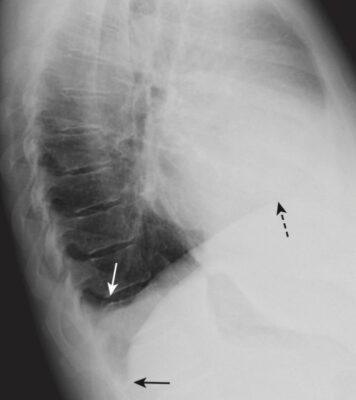

- Hình 3 hiển thị một số đặc điểm giải phẫu bình thường có thể nhìn thấy trên phim X quang ngực nghiêng.

- Nó có thể chứng tỏ bệnh lý không quan sát được trên phim thẳng (Hình 4).

- Trên phim nghiêng, có thể nhìn thấy cả rãnh lớn (chéo) và bé (ngang) dưới dạng các đường nhỏ, màu trắng (dày khoảng bằng đường kẻ bằng đầu bút chì). Các rãnh phân định các thùy trên và dưới ở bên trái và các thùy trên, giữa và dưới ở bên phải.

- Các rãnh lớn chạy theo hướng chéo, khoảng từ mức của đốt sống ngực thứ 5 đến một điểm trên bề mặt cơ hoành của màng phổi sau xương ức vài cm. Rãnh bé nằm ngang mức xương sườn thứ 4 trước (chỉ có ở bên phải) và hướng theo chiều ngang (xem Hình 3).

- Có thể nhìn thấy cả rãnh lớn và rãnh bé trên phim nghiêng, nhưng do mặt phẳng chéo của rãnh lớn nên thường chỉ có thể nhìn thấy rãnh bé trên phim thẳng.

Các góc sườn hoành sau (posterior costophrenic sulci)

- Mỗi nửa cơ hoành tạo ra một vòm tròn lõm vào phần trung tâm của đáy mỗi phổi giống như đáy của một chai rượu vang. Điều này tạo ra một chỗ hạ thấp, hay còn gọi là sulcus (ngách), bao quanh ngoại vi của mỗi phổi và là điểm thấp nhất của khoang màng phổi khi người bệnh ở tư thế dựng thẳng.

- Trên phim chụp X quang ngực thẳng, các ngách này dễ dàng nhìn thấy nhất ở rìa ngoài của phổi gọi là ngách sườn hoành bên (còn được gọi là góc sườn hoành bên) và trên phim chụp X quang nghiêng là ngách sườn hoành sau (còn được gọi là góc sườn hoành sau) (xem Hình 1 và 3).

- Thông thường, tất cả các ngách sườn hoành đều có đường viền sắc nét và góc nhọn.

- Tràn dịch màng phổi tích tụ trong các hốc sâu của ngách sườn hoành khi bệnh nhân ở tư thế dựng thẳng, sẽ lấp đầy các góc nhọn này, gọi là tù góc sườn hoành.

- Chỉ cần khoảng 75 mL dịch (hoặc ít hơn) để làm tù góc sườn hoành trên phim nghiêng, trong khi cần khoảng 250 đến 300 mL dịch để làm tù góc sườn hoành trên phim thẳng (xem Hình 10 và Bảng 3-1).